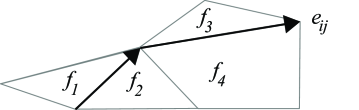

While curvature regularization term can be easily formulated in the local optimization frameworks, e.g. in a level set formulation (Leventon et al., 2000a) and Snakes’ model (Kass et al., 1988), it is much more difficult to incorporate such prior in a global optimization framework. Strandmark and Kahl (2011) proposed several improvements to approximate curvature regularization within a global optimization framework. They defined the curvature term as: , where is the boundary of the foreground region and is the curvature function. They approximated the above mentioned curvature term with discrete computation techniques by tessellating the image domain into a cell complex, e.g. hexagonal mesh, which is a collection of non-overlapping basic regions whose union gives the whole domain. They recast the problem as an integer linear program (along with a data term and length/area regularization terms) and optimized the total energy via linear programming (LP) relaxation. Figure 10(a) shows how Strandmark and Kahl (2011) discretized the image domain by cells. If , denotes binary variables associated to each cell region and denotes the boundary variable, then the curvature regularization term is written as a linear function: , where denotes the boundary pairs and

| (22) |

where is the length of edge and is the angle difference between two lines.